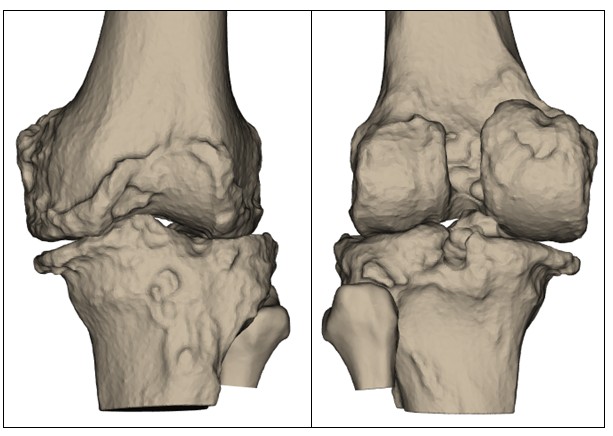

Before your surgery, your orthopaedic team will use advanced imaging techniques such as X-rays and a CT scan to create a precise 3D model of your knee. This digital reconstruction allows your surgeon to assess the specific anatomy of your joint in detail, including bone alignment, the degree of wear from arthritis, and any irregularities in joint movement. This model forms the foundation for a fully personalised surgical plan. Every decision, from where bone resections are made to how the implants are aligned is guided by your own anatomy. By tailoring the procedure in this way, the aim is to optimise implant positioning, restore natural joint movement, and enhance the long-term function of your new knee.